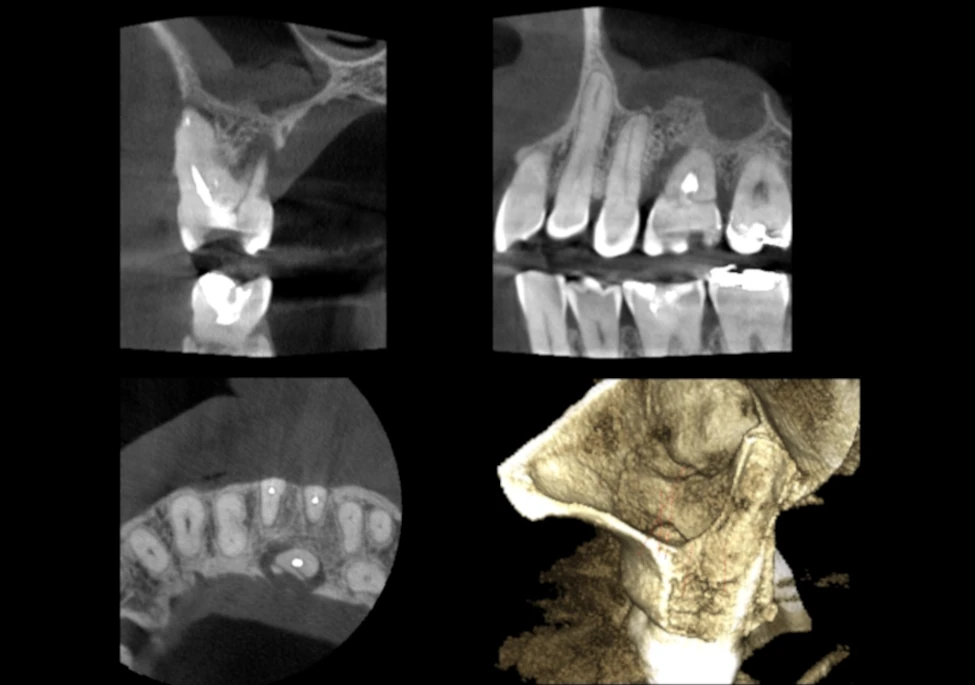

Planmeca ProMax® 3D Classic

Nuestra unidad Planmeca ProMax® 3D Classic cubre toda la dentadura, lo que la convierte en una excelente opción para las necesidades de imágenes 3D del arco dental completo

Nuestros equipos: Planmeca ProMax® 3D Classic

Calidad de imágen - Imágenes Tomográficas